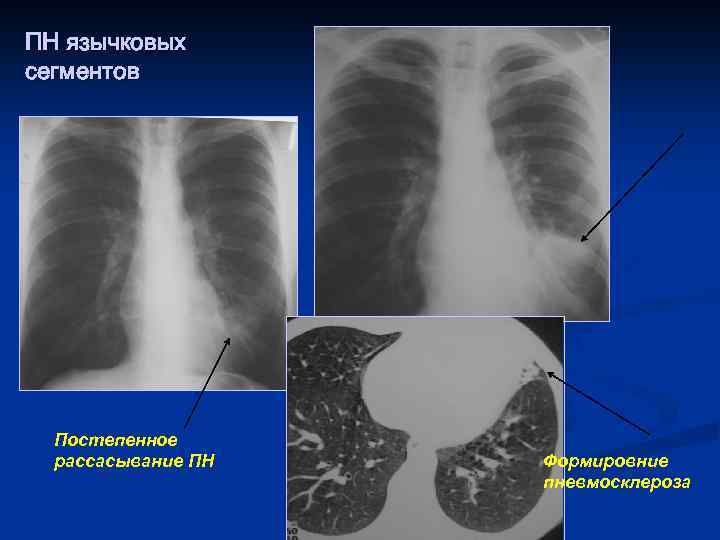

ПН язычковых сегментов Постепенное рассасывание ПН Формировние пневмосклероза